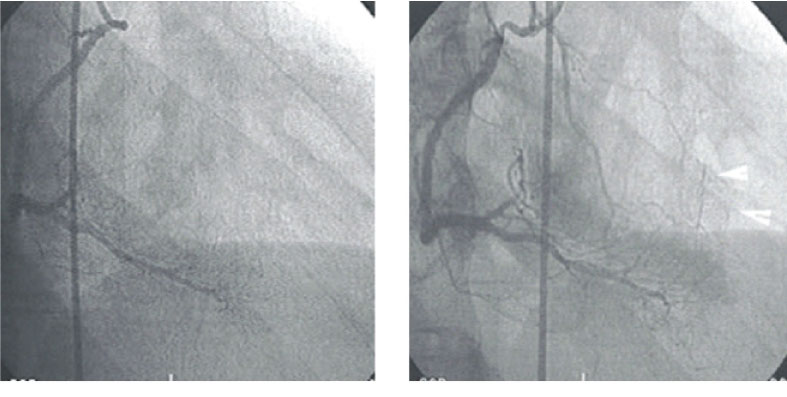

Increase myocardial perfusion and grow “Natural” Bypass.

Remarkable coronary collaterals presented from right coronary artery to the proximal segment of LAD, which had 90% stenosis before EHHT treatment for 36 hours.